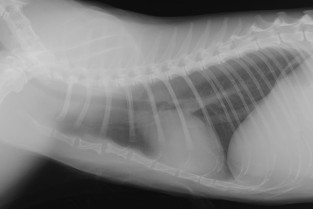

Cet atelier propose une approche concrète et structurée de l’interprétation radiographique du thorax, centrée sur la pratique clinique quotidienne. Après un bref rappel des fondamentaux par un intervenant diplômé européen en imagerie médicale, les participants seront amenés à travailler en petits groupes sur des cas cliniques sélectionnés pour leur complexité diagnostique, mais fréquemment rencontrés en consultation. Une occasion de consolider sa méthode de lecture, d’affiner son œil critique et d’éviter les pièges.

- Appliquer une méthode structurée de lecture radiographique du thorax chez le chien et le chat.

- Reconnaître les images radiographiques normales et les principales variations physiologiques.

- Décrypter des cas complexes, et en discuter les diagnostics différentiels.

- Éviter les pièges fréquents d’interprétation en tenant compte des limites de la radiographie.